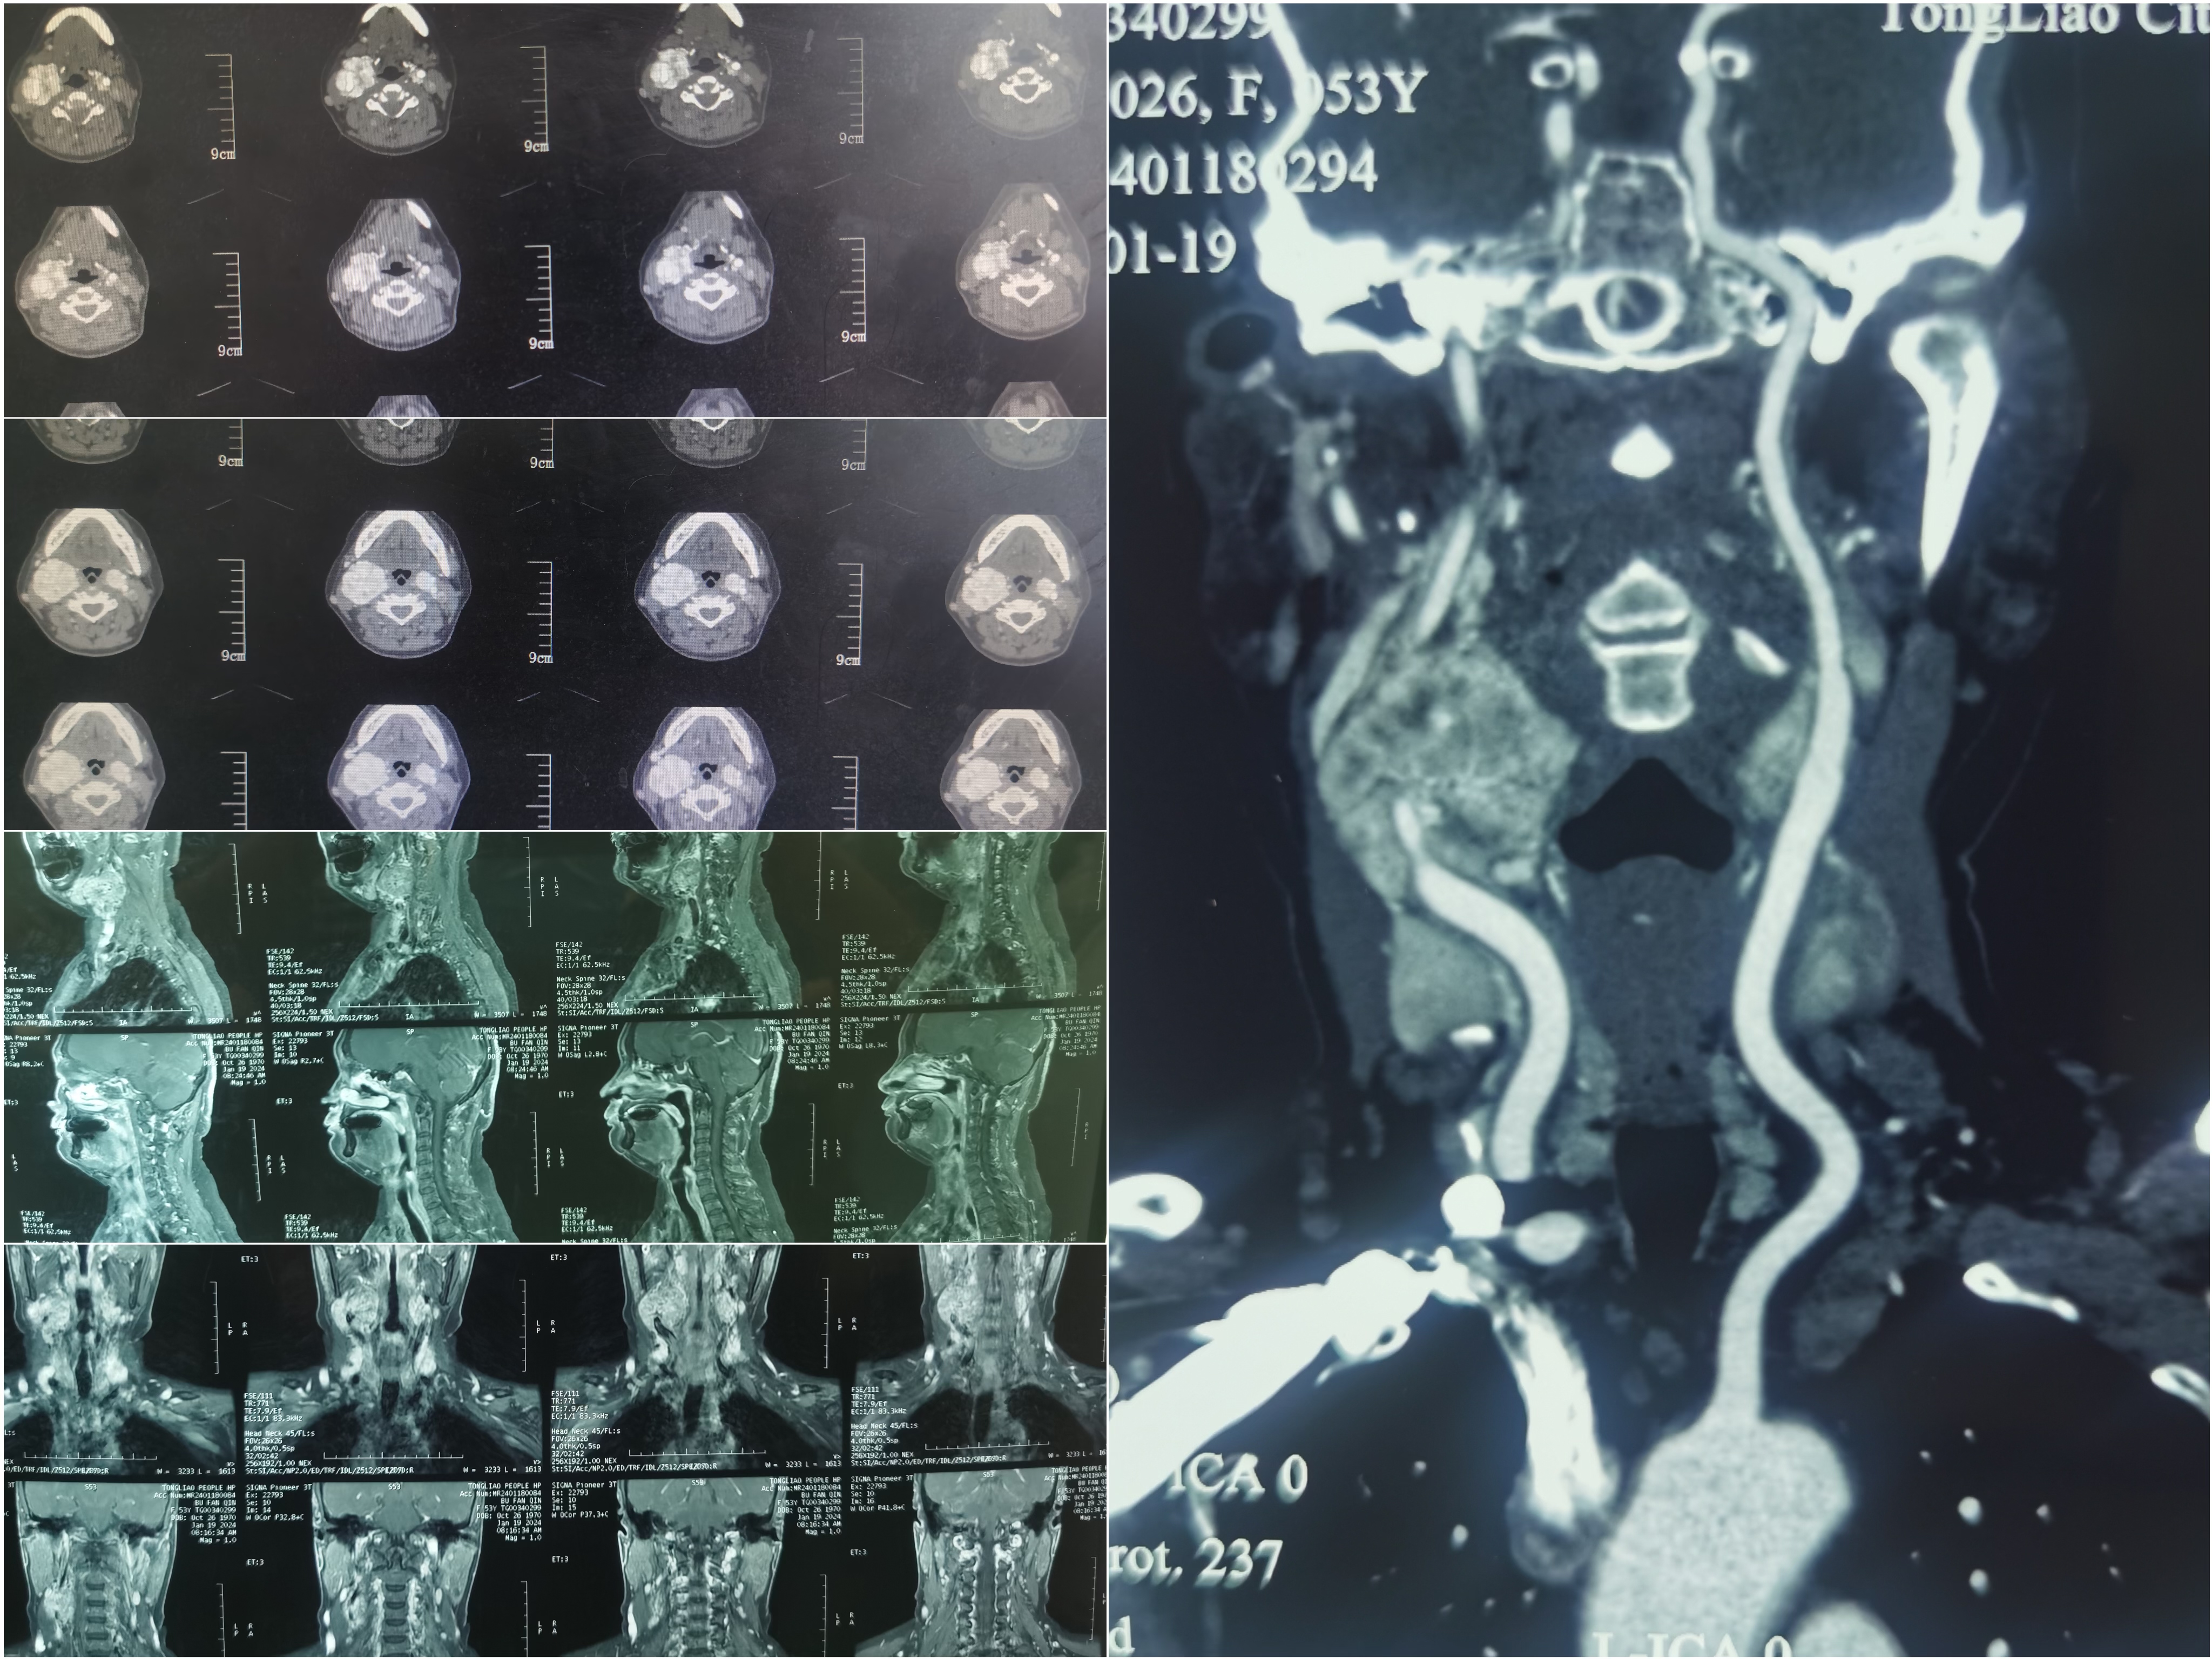

患者,女性,53岁,主因8年前发现右侧颈部较小包块,未予重视及治疗,近一年来右侧颈部包块明显增大,已严重影响日常生活,来到我院神经外科寻求治疗。经过赵林主任详细询问病史及系列检查后诊断为“颈动脉体瘤”。患者及家属表示非常信任我院神经外科团队并要求手术治疗。

科室住院医师高岩为患者进行了系统的术前检查。因患者病史较长,右侧包块较大且与周围组织粘连严重,增加了手术难度及风险,赵林主任组织全科医师进行术前讨论,充分评估术中风险及制定周密的手术计划。建议先手术处理右侧较大的包块,待患者病情恢复良好再进行对侧包块手术,患者及家属表示同意。赵林主任团队在全麻下为患者行“右侧颈动脉体瘤切除术”,在麻醉师单志婧及手术室团队的默契配合下,肿瘤完整切除,手术顺利结束。术后患者无神经功能缺失,颈动脉血流良好,持续8年的病痛得以解除。患者及家属对赵林主任及神经外科团队的辛苦表达了诚挚的感谢并表示待康复后来院进行对侧颈动脉体瘤切除治疗。